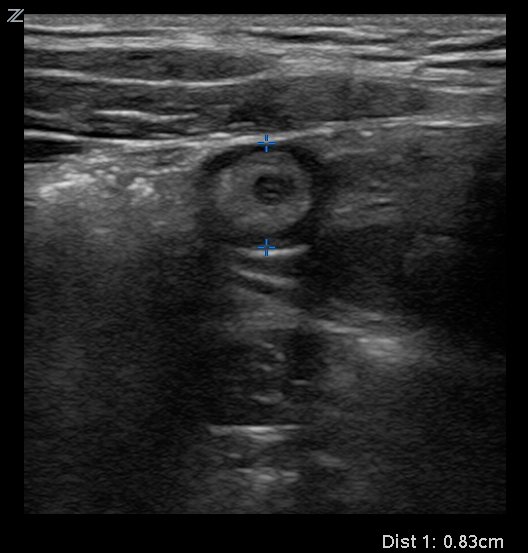

24yo F G2P1011 with hx of kidney stones presents complaining of right sided abdominal pain. The goals for this case are to recognize potential causes of right sided abdominal pain and the utility of using bedside US to narrow your differential and ultimately obtain your diagnosis.